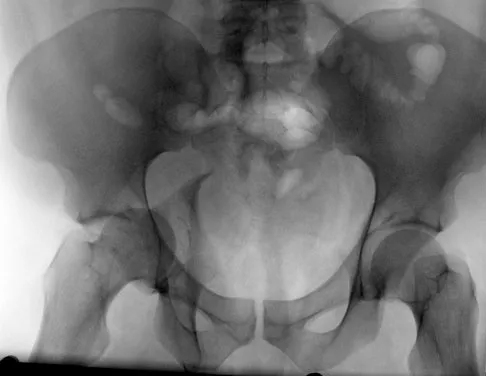

Which of the following choices best describes the fracture pattern shown in Figures 2a through 2c?

Explanation

The fracture pattern shown in the radiographs is a fracture of the posterior column. The only line interrupted on the AP pelvis is the ilioischial line. The obturator oblique view shows that the iliopectineal line is intact as is the outline of the posterior wall. The iliac oblique view shows an interruption of the ilioischial line and an intact anterior wall. Therefore, this fracture is a fracture of the posterior column. Letournel E, Judet R: Fractures of the Acetabulum, ed 2. Berlin, Germany, Springer Verlag, 1993.